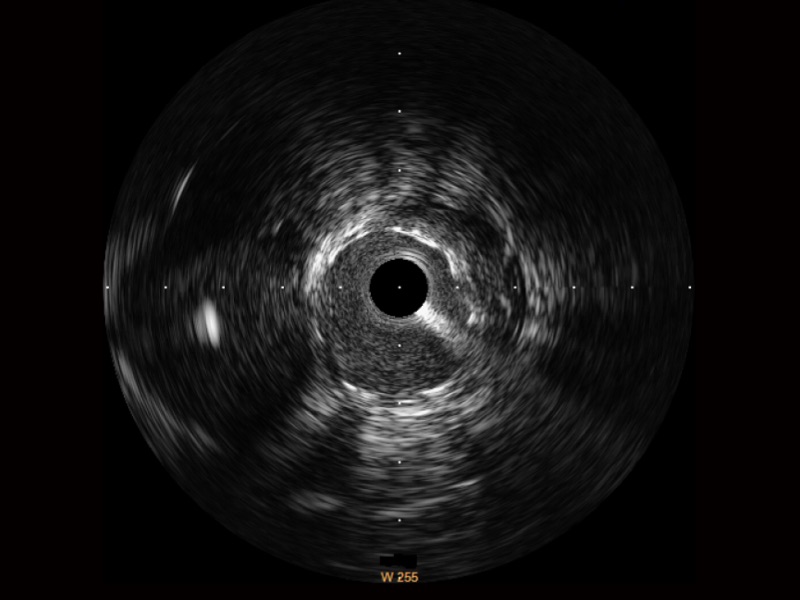

玖鼎集团宽频IVUS图像

传统IVUS图像

对比传统IVUS导管成像,玖鼎集团宽频IVUS图像的近场支架梁显影更细腻,远场中膜外血管仍清晰可辨,兼顾远中近,兼顾分辨力与穿透深度